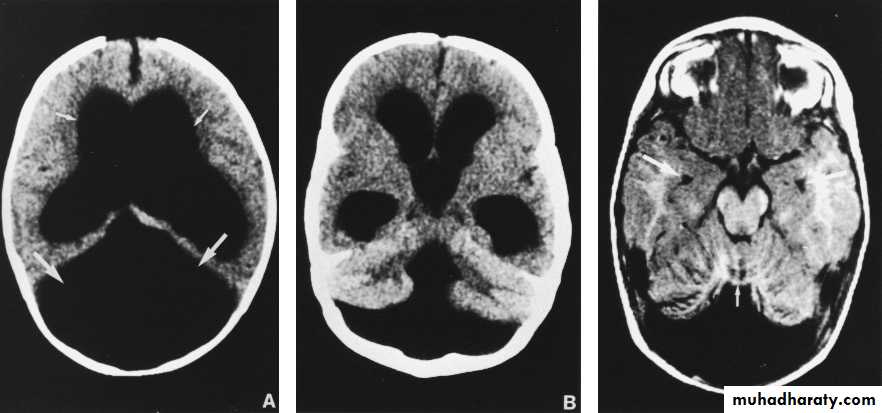

Transullimation of the skull +ve; Dandy walker.

Inspection of eye ground; chorioretinitis suggest IU infection as toxoplasmosis.

INV:

Skull X-ray:Seperation of sutures

Errosion of posterior clinoid

CT/MRI/US: Dx specific Cause.

Dandy-walker